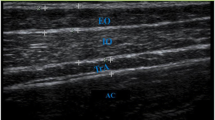

Regions of interest (ROIs) were manually drawn around the SF, muscle compartment (Figure 1B), and five individual muscles; the soleus, medial gastrocnemius, lateral gastrocnemius, tibialis anterior, and tibialis posterior (Figure 1C), on the mDixon water images using Osirix version 3.7.1 [25]. SF volume was normalised to muscle volume (Equation 1), creating a SF to muscle volume ratio (SF/M). The ROIs around the entire musculature and individual muscles were eroded with a structuring element size of 2 pixels (4.0 mm) to remove any potential edge effects with surrounding subcutaneous fat (or intermuscular fat for IntraMF quantification). IMAT and IntraMF were calculated using a ratio of the water and fat signal intensities within the eroded ROIs (Equation 2). The reproducibility of the Dixon technique employed was measured using 5 acquisitions of one TD subject imaged over 3 visits, with the scan repeated twice during 2 of these visits. Reproducibility was defined as the average standard deviation of the measured percentage fat, i.e. the standard deviation averaged across all muscles investigated.

Image segmentation: (A) Example mDixon water image; (B) manually drawn region of interest (white) for the muscle compartment for IMAT segmentation; and (C) the 5 muscles analysed drawn around tibialis anterior (TA), tibialis posterior (TP), soleus (SOL), medial gastrocnemius (MG) and lateral gastrocnemius (LG) for IntraMF segmentation.